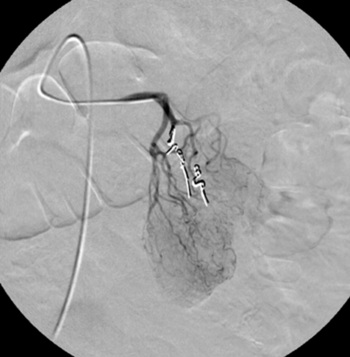

Digitale Subtraktionsangiografie: In der Leber zeigen sich multiple pathologische Anreicherungen, die Tochtergeschwülsten eines Karzinoids entsprechen.

Digitale Subtraktionsangiografie: Einen Monat nach der erfolgten Chemoembolisation, bei der direkt in die Leberarterie ein Medikament zur Tumorbehandlung gegeben wurde (TACE), stellen sich die zuvor zahlreichen Metastasen nicht mehr dar.